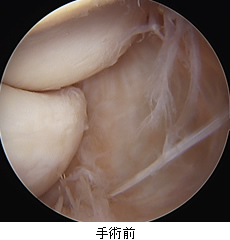

肩の痛みは外来で遭遇する頻度の高い症状です。多くは肩関節周囲炎(いわゆる四十肩・五十肩)によるものですが、一部には肩関節の周囲に存在する腱板という組織が損傷していることにより痛みが出ている場合があります(腱板断裂または損傷)。加齢性の変化で切れる場合や、外傷性の場合、また肩を使う仕事やスポーツなどにより摩耗して切れる場合があります。保存治療を行なっても痛みが続く場合、関節鏡を用いた腱板の修復術が行われます。

A: 腱板断裂部(上に見えているのが断端。下に上腕骨が見えている(黒丸部)。)